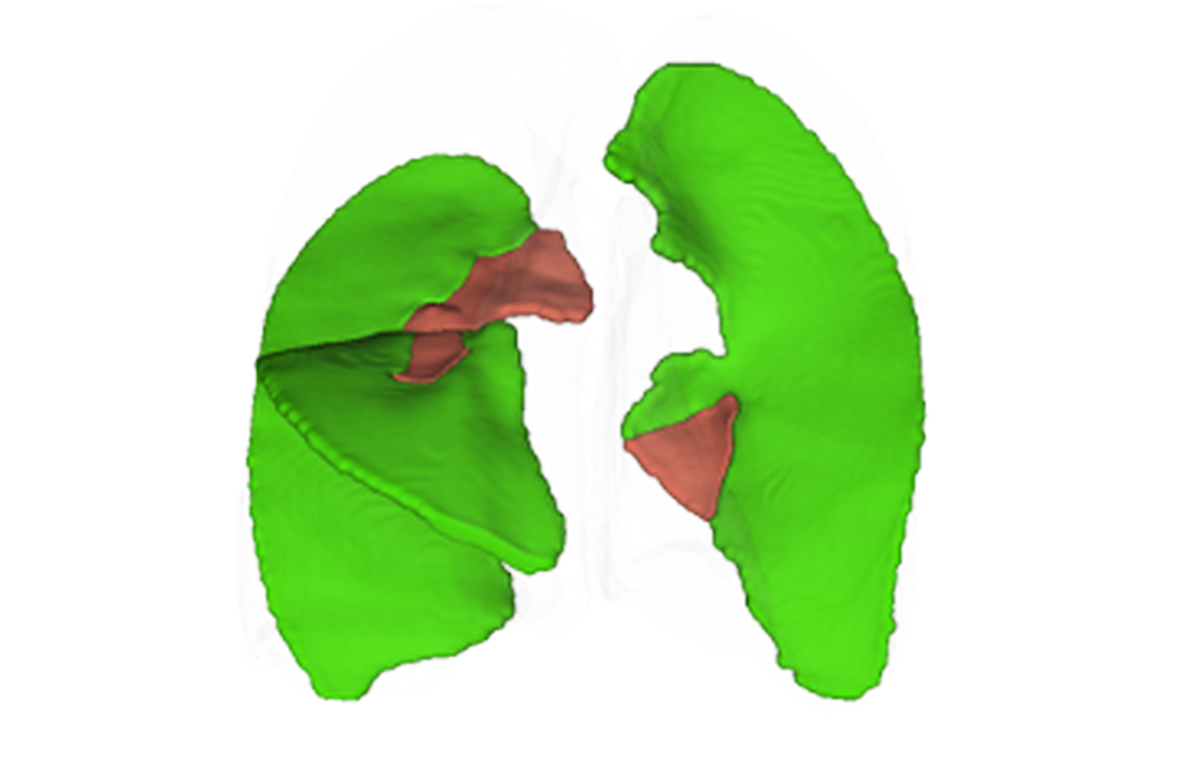

Built on advanced capabilities in lung segmentation and quantification, our AI technology interprets thoracic CT data with anatomical precision - capturing airway trees, parenchymal patterns, and vascular structures, even in severely diseased lungs.

- Segmentation of anatomical structures up to sub-segmental level

- Anatomical mapping to support navigation planning and guidance